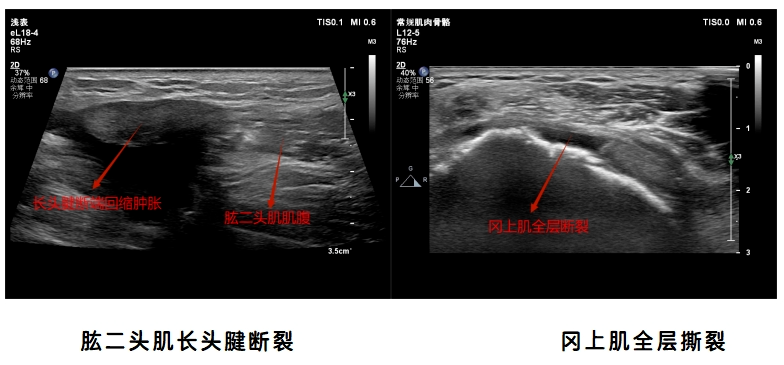

1.肩关节超声检查:肩袖损伤、肌腱病、粘连性关节囊炎(肩周炎)、肱二头肌长头腱肌腱炎及脱位、肱二头肌断裂、肩锁关节炎等。

病例图像